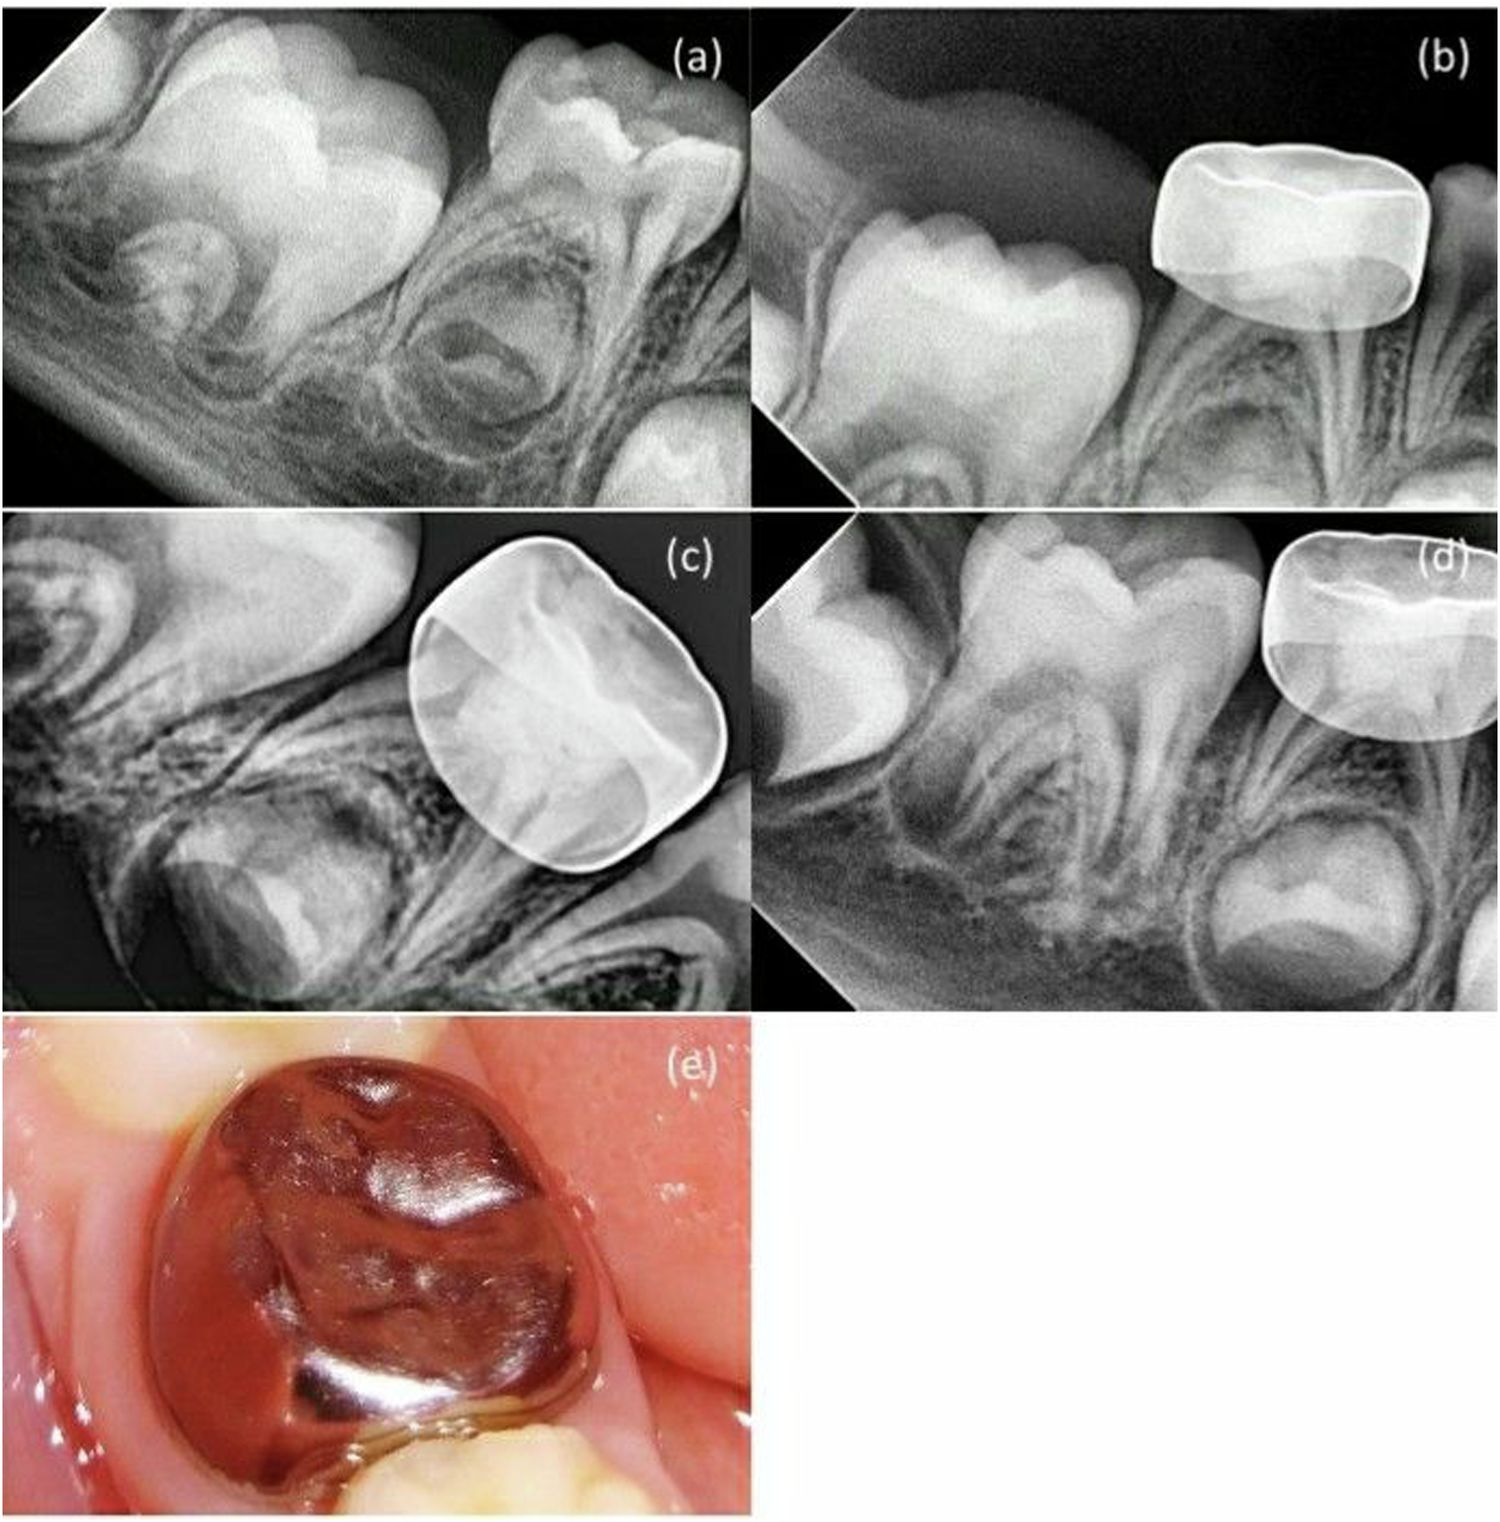

Fig. 2: MTA + NaOCl gel group in second primary molar pulpotomy in a female participant aged 5 years.

a A preoperative radiograph. b 3-month follow-up. c 6-month follow-up. d 12-month follow-up. e A photograph after 12-month follow-up.